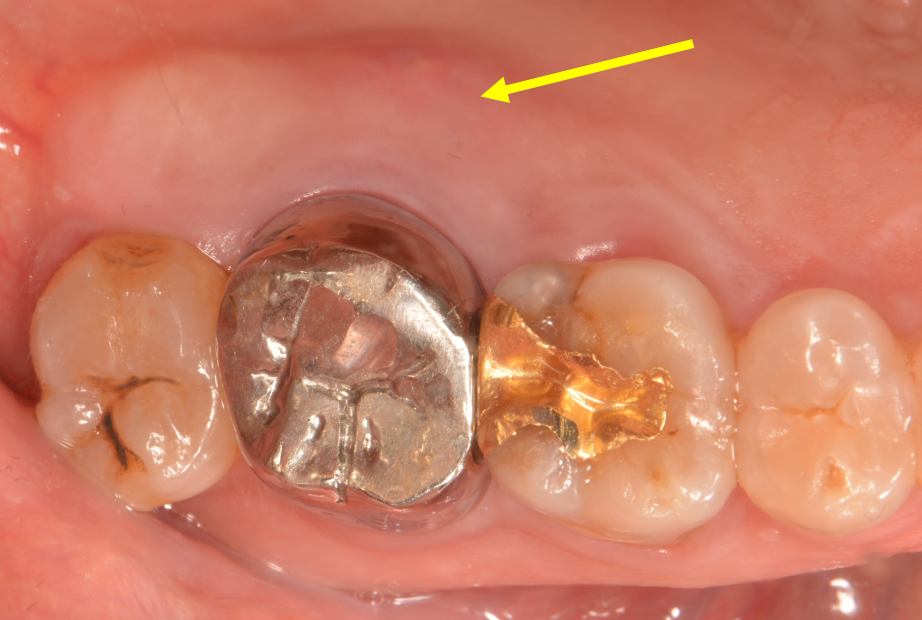

치주 농양 치료

After

원래도 치조골이 소실되었거나 해서 잇몸 속으로 깊은 주머니(치주낭)가 있는 경우에

면역력이 떨어지거나 하면 크게 붓고 아픈 치주 농양이 생길 때가 있습니다.

이럴 때는 얼른 치과에 오셔서 잇몸치료 및 소독, 항생제 처치 등을 받으시면

조기에 통증 경감 및 증상 개선을 얻으실 수 있습니다.